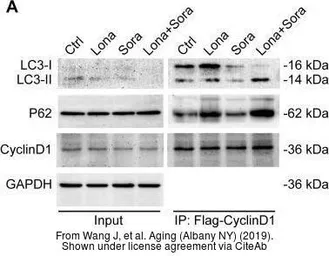

The data was published in the Cancer Med in 2020. PMID: 32324343